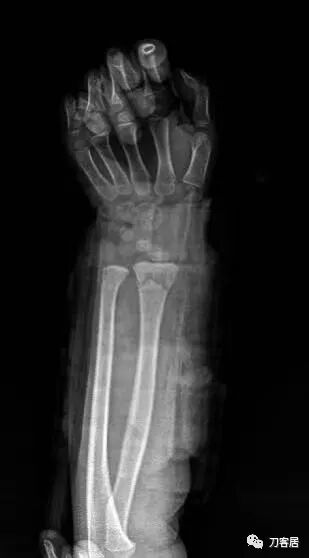

下面是这个6岁孩子,尺桡骨远端双骨折的术前及术后片子和外观照片。

1.  这是一个很简单的6岁儿童无移位的尺桡骨远端骨折。没有皮肤损伤,没有移位,没有骨折碎块儿。

2.  这个骨折处理起来也很简单,单纯的打石膏托或者中医的小夹板,或者正规的包括腕关节和肘关节的管型石膏外固定4周即可治愈该骨折。实在不行,如果这个孩子比较听话,不太调皮的话,用一本书,一个三角巾悬吊固定4周,都可以治愈该骨折。但是给这个患者用外固定架做了手术,而且桡骨远端的几颗克氏针距离骨折线太近,其中一枚克氏针进入到骨折间隙内。从这个术中图片来看,术者的外固定手术技术也有待于进一步的提高。毕竟术者应该还很年轻。从X线片来看,前臂及手的尺侧有不透光影,应该还使用了外固定石膏绷带托,而且我猜测应该是高分子的石膏绷带托,这个是纯属猜测,不一定是对的,不过如何解释前臂尺侧的不透光影呢?如果真是用了石膏绷带外固定的话,那为啥要做手术呢?外固定架术后就不该再用石膏绷带托辅助了。

3.  对于肢体骨折,特别是前臂长骨骨折,双骨折虽然不稳,但更容易手法复位,往往单骨折手法复位比较困难。该病例患儿6岁,尺桡骨双骨折,没有移位,所以根本就不存在需要复位的,直接打石膏外固定即可。孩子年龄越小,塑形能力越强,愈合速度越快,即使是有轻度的畸形骨愈合,在未来的塑形过程中,自然而然的恢复正常的力线和功能。对于该病例,即使是不干预,再过1-2周,只要骨折断端不移位,也能正常愈合而不留任何畸形。